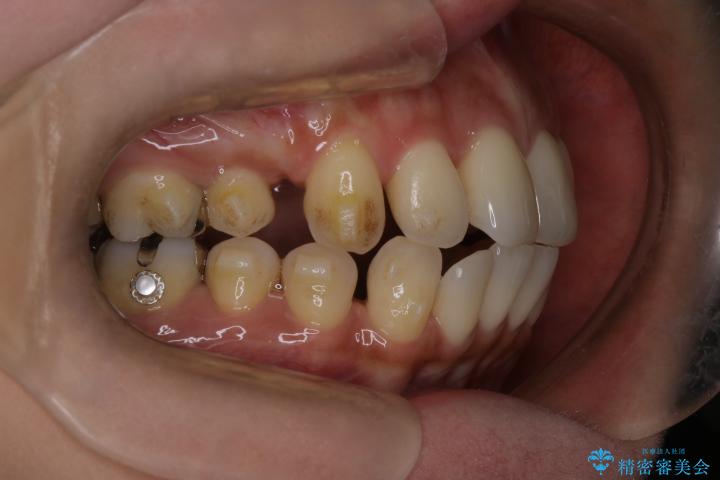

治療途中

• 上顎前歯の突出を軽減 インビザラインによる抜歯矯正 治療途中画像

インビザラインにて抜歯矯正を行うと、高頻度で奥歯が咬み合わなくなります。

また、抜歯スペースに向けて奥歯が移動する際、必ず傾斜して移動するため、仕上がりの咬み合わせはワイヤー矯正と比べて明らかに劣ります。